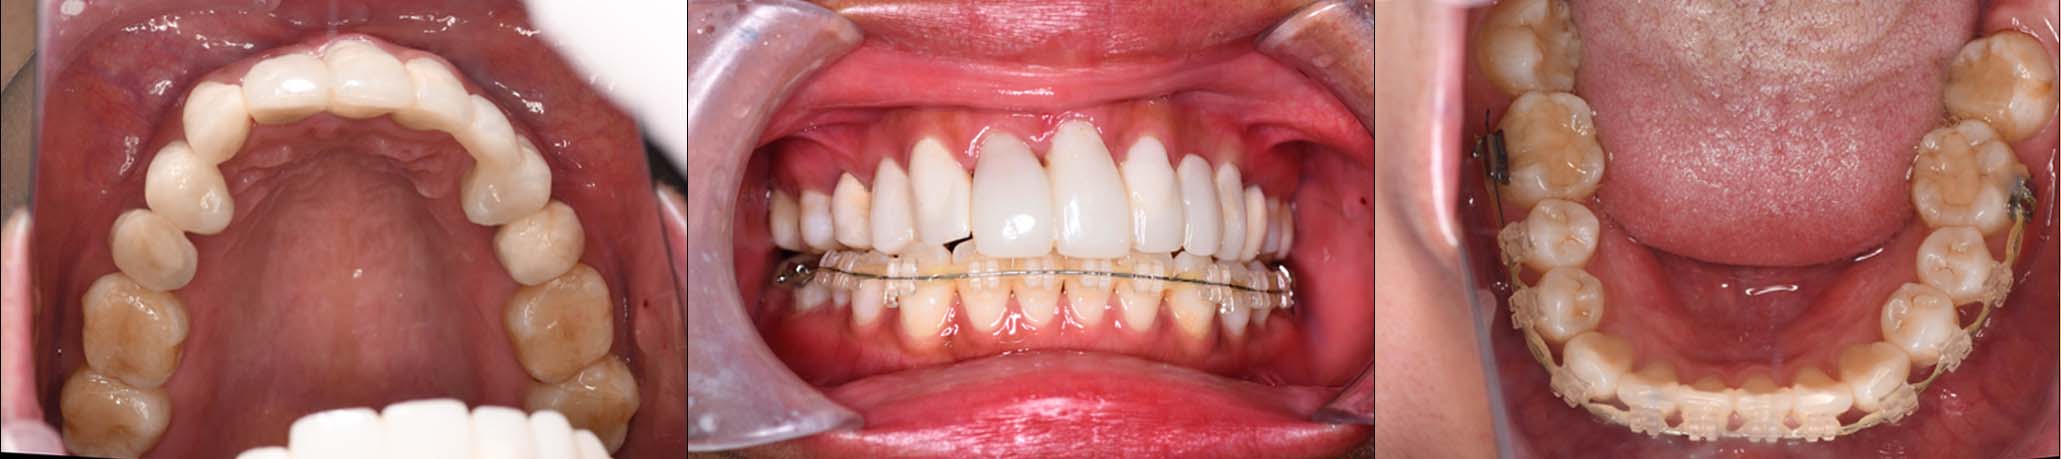

12月16日

12月23日

1月9日

1月30日

2月20日